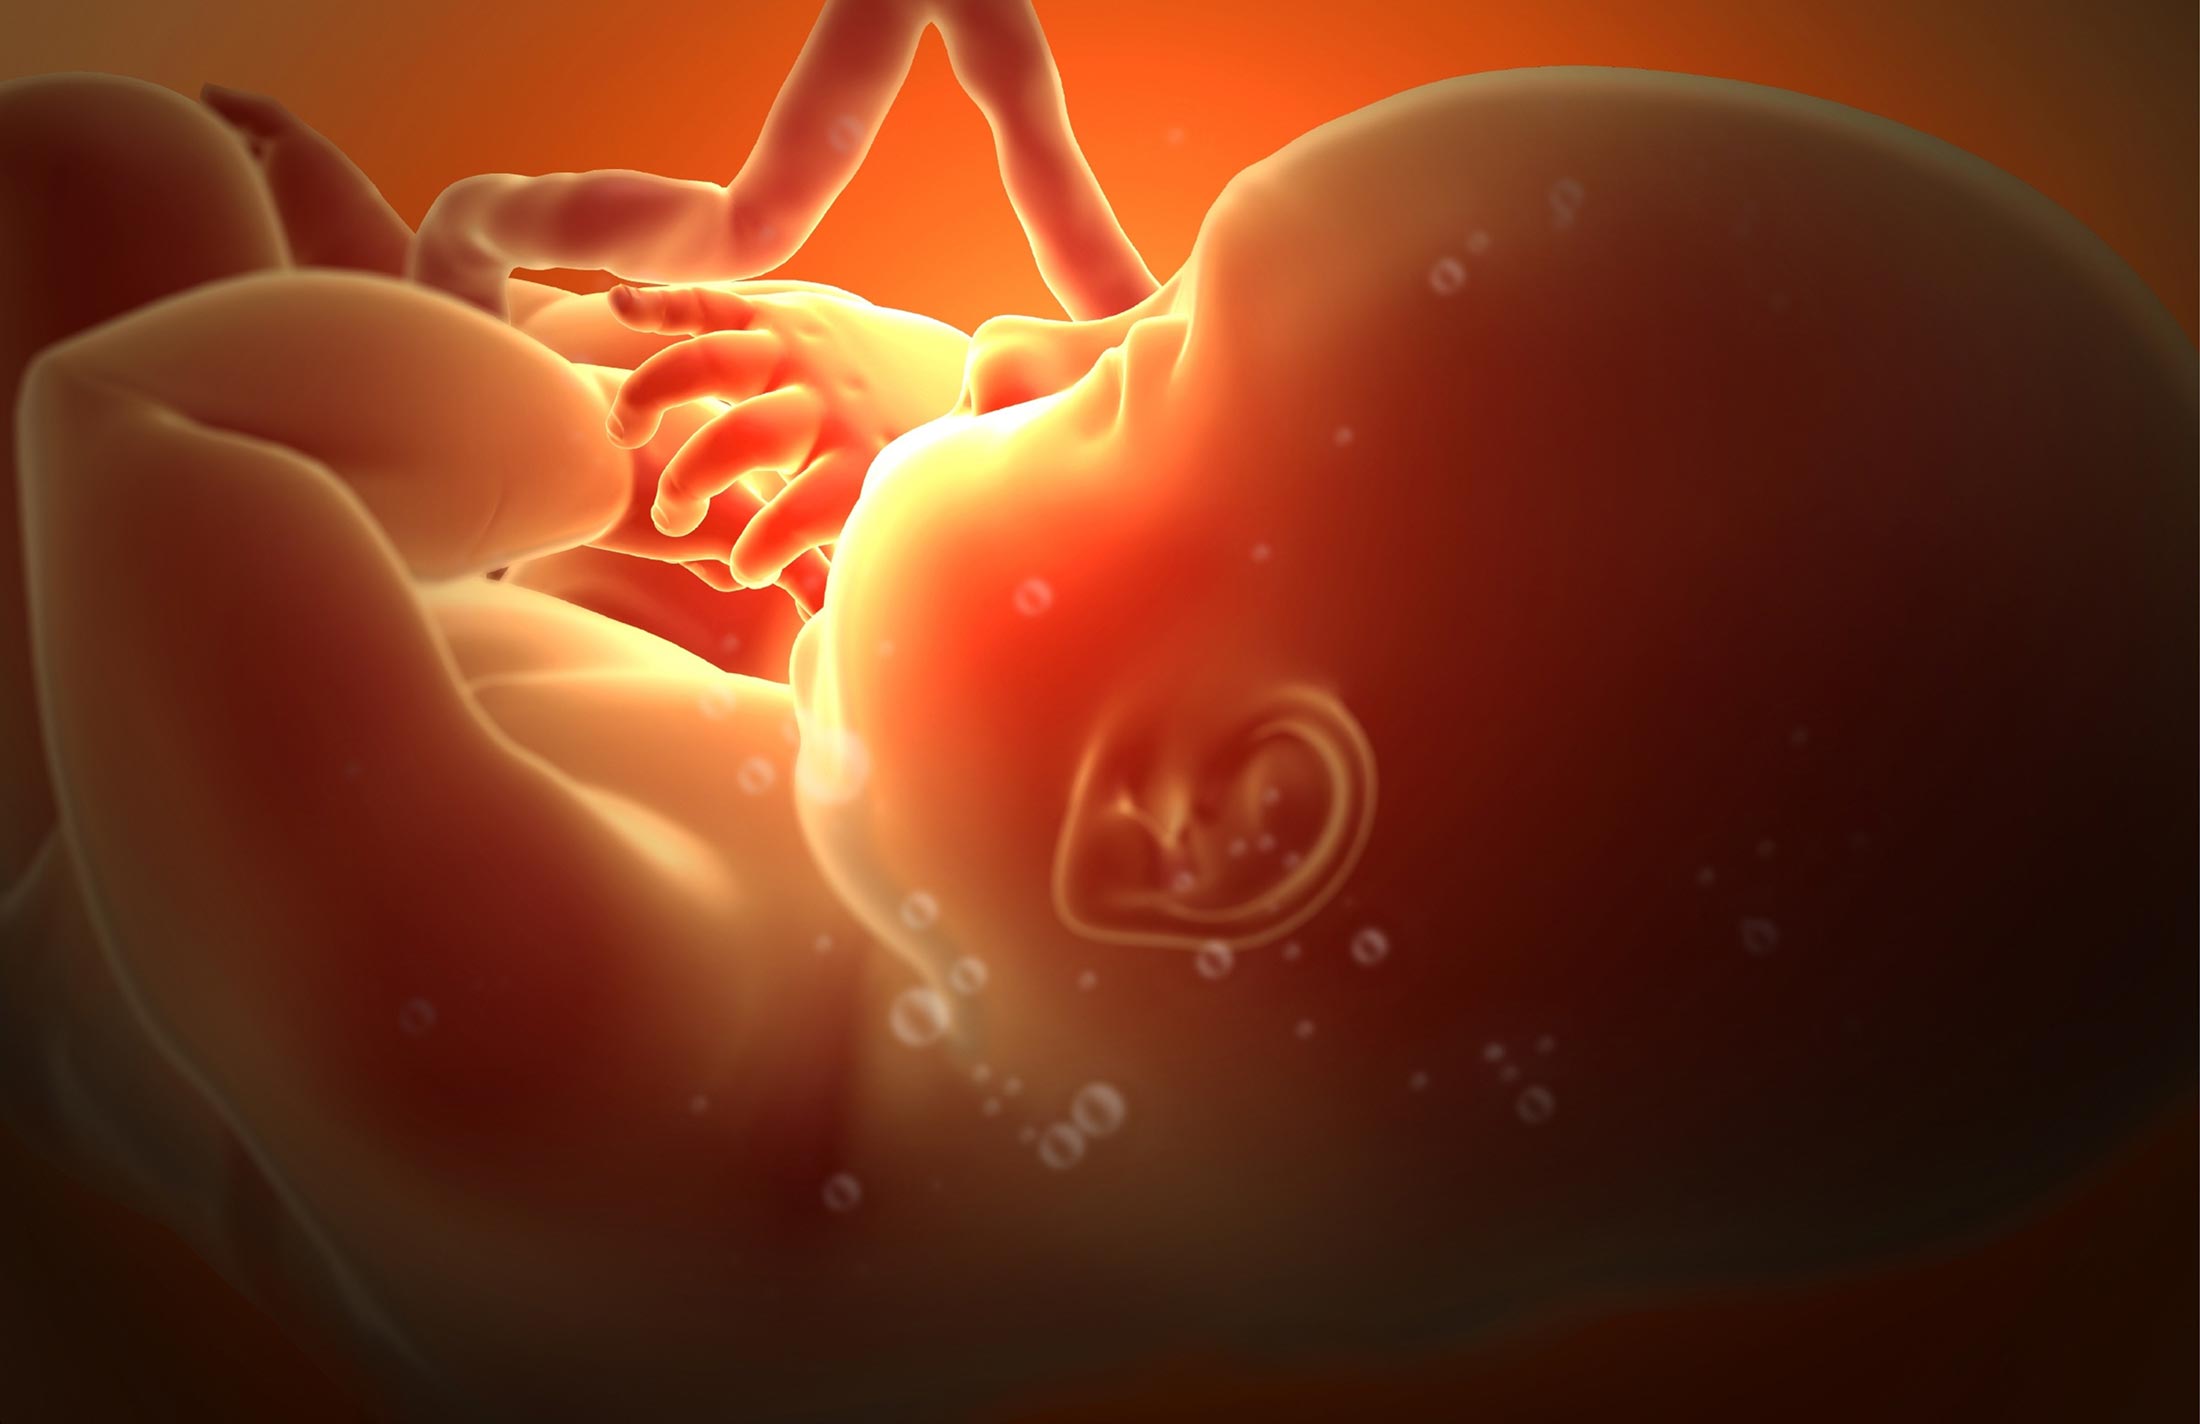

Загадочные образы животных в утробе матери